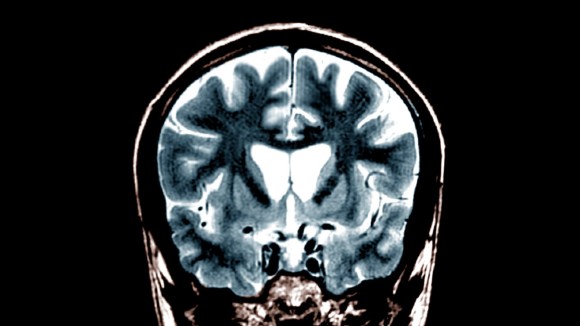

Amsterdam, Belanda - Penyakit Huntington adalah gangguan otak yang diwariskan dan progresif, menyebabkan hilangnya kontrol koordinasi dan fungsi kognitif yang memburuk seiring waktu. Penyakit ini disebabkan oleh mutasi genetik yang memproduksi protein cacat beracun bagi neuron di otak, khususnya pada bagian yang disebut striatum.

UniQure mengembangkan terapi gen baru yang menggunakan virus untuk mengantarkan mikroRNA ke dalam sel otak. MikroRNA tersebut bertugas membungkam gen cacat huntingtin sehingga produksi protein beracun dapat dihentikan, dan terapi ini hanya diberikan satu kali melalui operasi khusus.